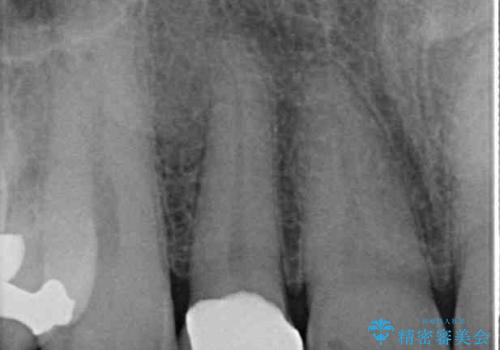

- 内側に倒れている前歯が擦れてしみるとのことで来院された患者様です。

削れていた部分は詰め物が入っていましたが、縁の部分がしみているようで、変色も目立っていたため、オールセラミッククラウンにて補綴治療を行うこととしました。